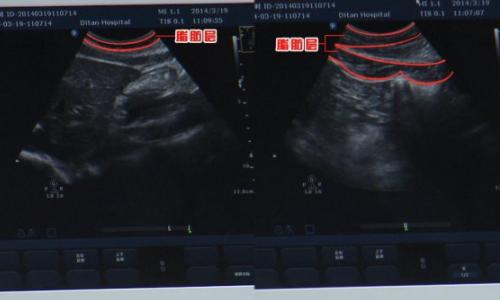

肥胖會對我們的身體造成巨大的危害,如肝、骨、以及內(nèi)分泌等各個方面,通過專家?guī)韺I(yè)設(shè)備,我們可以很容易的看到肥胖者和正常人群體內(nèi)脂肪的狀態(tài)。更多內(nèi)容請收看本期節(jié)目。